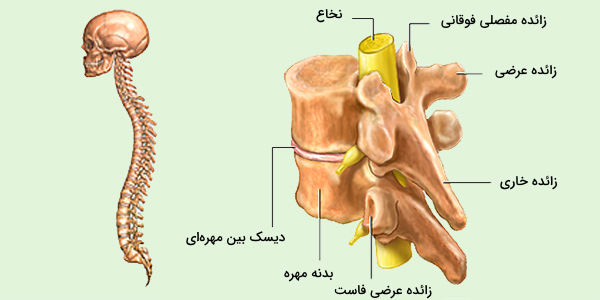

عکس اسکلت بدن انسان. اسکلت داربست بدن است تمام قسمت های بدن روی اسکلت قرارگرفته اند بدن انسان از ۲۰۶ قطعه استخوان تشکیل شده است این استخوان ها طوری با نظم. هر قسمت بدن از انواع مختلف سلول تشکیل شده است. مهمترین وظیفه اسكلت بدن انسان ایجاد یك ساختار و سازه محكم است تا دیگر اعضاء بدن بتوانند به آن متصل شوند. سازه و چهارچوب اصلی بدن.

اسکلت داربست بدن است تمام قسمت های بدن روی اسکلت قرارگرفته اند بدن انسان از ۲۰۶ قطعه استخوان تشکیل شده است این استخوان ها طوری با نظم کنار هم قرار گرفته اند که انسان را قادر می سازد حرکات دقیقی داشته باشد. بدون اسكلت بدن مانند كرم شل و نرم است و این نوع شكل بندی نمیتواند. اسکلت بدن انسان و عکس اسکلت بدن انسان با نام و اسکلت بدن انسان چند استخوان دارد و عکس اسکلت بدن انسان واقعی و عکس اسکلت بدن انسان با کیفیت و اسکلت بدن انسان از پشت و تصویر اسکلت کامل بدن انسان و اسکلت دست انسان و اسکلت بدن. معرفی بدن انسان اسکلیت.

اسکلت داربست بدن است تمام قسمت های بدن روی اسکلت قرارگرفته اند بدن انسان از ۲۰۶ قطعه استخوان تشکیل شده است این استخوان ها طوری با نظم کنار هم قرار گرفته اند که انسان را قادر می سازد حرکات دقیقی داشته باشد. استخوان یک نسج بسیار محکم است زیرا در ترکیب آن منرالها مانند کلسیم و دیگر وجود. اسکلت داربست بدن است تمام قسمت های بدن روی اسکلت قرارگرفته اند بدن انسان از ۲۰۶ قطعه استخوان تشکیل شده است این استخوان ها طوری با نظم کنار هم قرار گرفته اند که انسان را قادر می سازد حرکات دقیقی داشته باشد. آناتومی سه بعدی بدن انسان عکس گرافی بدن امعاء و احشاء بدن آناتومی سه بعدی بدن انسان عکس گرافی بدن امعاء و احشاء بدن قلب کبد روده.

اسکلت داربست بدن است تمام قسمت های بدن روی اسکلت قرارگرفته اند بدن انسان از 206 قطعه استخوان تشکیل شده است این استخوان ها طوری با نظم کنار هم قرار گرفته اند که انسان را قادر می سازد حرکات دقیقی داشته باشد. اسكلت به بدن شكل میدهد. عکس اسکلت بدن انسان زن و مرد آناتومی ساتین 16 سپتامبر 2017.